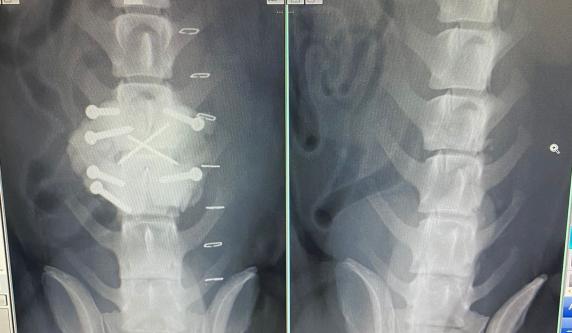

SIDNEY 2280908 male, 25.10.2022., in the shelter since 27.11.2023., from streets of the village where he was hit by a car, his spine was injuried.  He is a miracle dog! Becuase he was operated, and he walked with wheelchair, but now he walks by himself and doesn't need wheelchairs anymore! He just cannot control pipi and kaka by himself.  He is very loyal and attached, loves attention and people, loves cuddles, and to be held in the arms. He adores to play with balls, and ball was the biggest motivation for him to start to walk. He is good with other dogs. Foster home Alex, and she can say more about him.  Cca 35cm